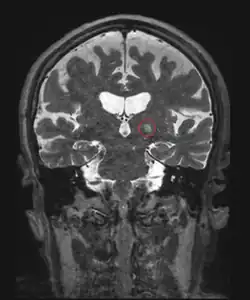

Le traitement des lésions intracérébrales par ultrasons focalisés est difficile en raison de la barrière osseuse (crâne), qui déforme les faisceaux ultrasonores. Les premiers tests, qui remontent aux années 1950 ont ainsi été réalisés à travers une ouverture pratiquée dans le crâne[15]. L'utilisation de réseaux de transducteurs avec correction numérique de la distorsion osseuse basée sur des données tomodensitométriques du crâne a permis de focaliser les ultrasons à travers un crâne intact[16] et d'expérimenter la technique sur des tumeurs cérébrales[17].

Maladies neurologiques

La destruction ou la section de certaines petites structures cérébrales par chirurgie stéréotaxique permet d'améliorer certaines maladies neurologiques. Les HIFU, guidées par imagerie par résonance magnétique[21] semblent être une alternative moins lourdes et ont été testées dans plusieurs maladies : douleurs neuropathiques (section du thalamus centrolatéral[22]), tremblements essentiels (thalamus[23],[24]) et maladie de Parkinson (faisceau pallidothalamique (en) [25].) La technique non invasive concurrente reste la radiochirurgie où la lésion est obtenue par un rayonnement radio-actif.